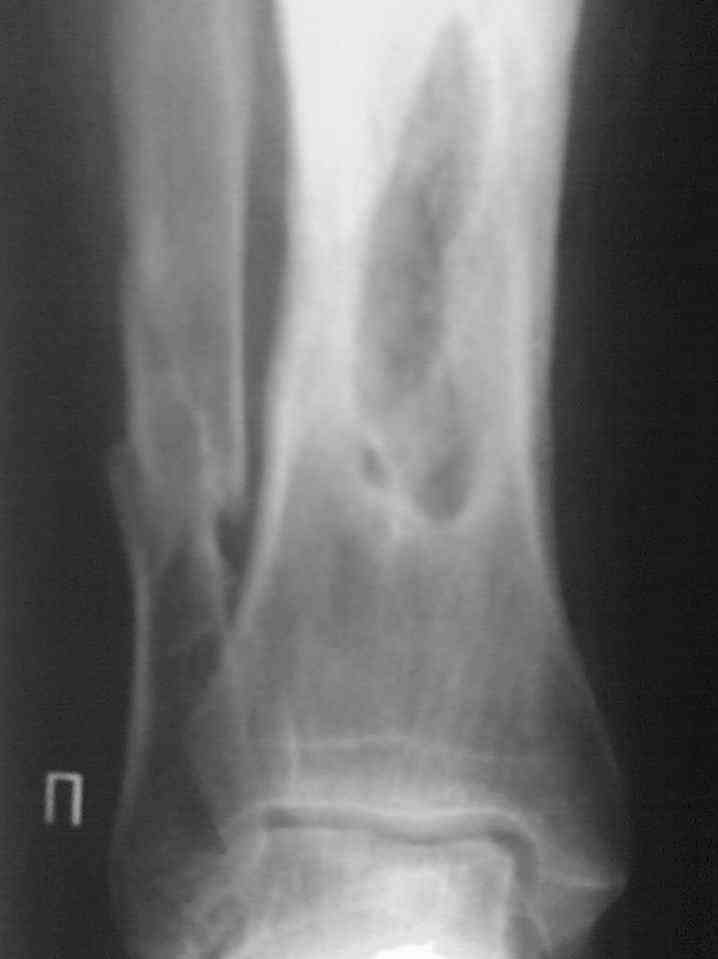

Выкладываю снимки в хронологическом порядке. Снмки все какие есть у больного.

Количество не заменяет качества, поэтому не стоит выкладывать весь хлам, какой удастся найти у пациента. Лучше сделать 1)свежие 2)хорошего качества рентгенограммы, чтобы оценивать ситуацию по ним, а не по мутным огрызкам.